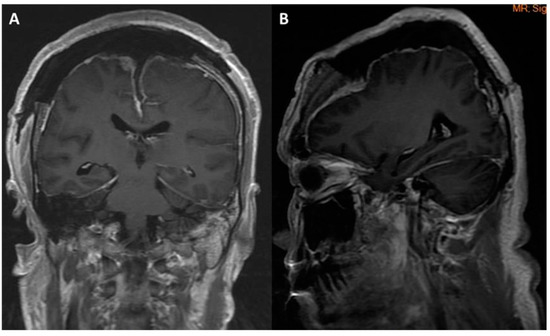

| Tsai et al., 2021 | 55/M | Seizure, loss of consciousness | 91 | bilateral | occluded | II | I | 2/5 left arm and left leg 0/5 right leg | Preserved | Aphasia | Aphasia recovery within 7 days; muscle power recovery within 7 weeks |